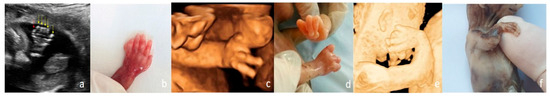

From Diagnosis to Decision—Fetal Limb Abnormalities

by Andreea Florentina Stancioi-Cismaru, Razvan Grigoras Capitanescu, Mihaela-Simona Naidin, Cristian Constantin, Marina Dinu, Florin Burada, Oana Sorina Tica, Mihaela Gheonea, Bianca Catalina Andreiana, Razvan Cosmin Pana and Stefania Tudorache

J. Clin. Med. 2026, 15(2), 486; https://doi.org/10.3390/jcm15020486 - 8 Jan 2026

Background/Objectives: Our aim was to investigate the diagnostic accuracy of prenatal ultrasound (US) in fetal limb abnormalities. As a secondary target, we wanted to correlate various predictors for the diagnosis accuracy. Methods: We prospectively enrolled cases with routine prenatal US performed in five [...] Read more.

Background/Objectives: Our aim was to investigate the diagnostic accuracy of prenatal ultrasound (US) in fetal limb abnormalities. As a secondary target, we wanted to correlate various predictors for the diagnosis accuracy. Methods: We prospectively enrolled cases with routine prenatal US performed in five participating centers. Subsequently, we selected and processed all cases with limb abnormalities: suspected, diagnosed, and missed on the prenatal diagnosis scans. We collected data on the type of anomaly, the US equipment and probes used, the operator’s expertise, the gestational age at the diagnosis, the length of the examination, and the use of US reporting form. SPSS 22.0 software was applied to perform the analyses using non-parametric statistical methods. Associations between categorical variables were evaluated using Fisher’s exact test and Chi-square tests. For correlations between the gestational age and the anomaly severity, we used Spearman’s rank-order correlation. Predictive performance of operator- and scan-related variables for diagnostic accuracy was assessed using receiver operating characteristic (ROC) curve analysis, with area under the curve (AUC) estimates, standard errors (SE), confidence intervals (95% CI), and p-values reported. Results: Our data showed that most US examinations were performed as part of routine screening (79.7%), and the most frequent anomaly diagnosed was clubfoot. Operators’ expertise demonstrated the highest predictive performance, while technical parameters—scan duration (AUC = 0.20, p = 0.1188) and US equipment (AUC = 0.30, p = 0.3478)—did not significantly predict diagnostic accuracy. Conclusions: The overall diagnostic accuracy of prenatal US was 85.5%. Our findings indicate that diagnostic performance is driven primarily by operator expertise and training, rather than by gestational age at scan and technical parameters. Full article

Show Figures

Figure 1